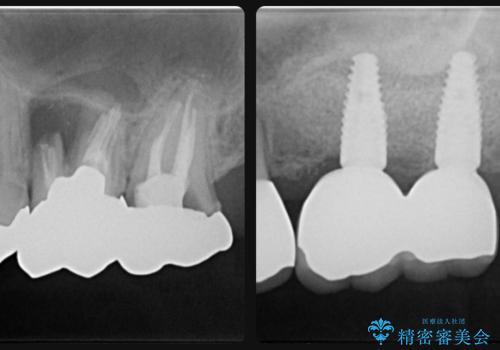

薄い歯質の歯牙に過大な負荷がかかり亀裂を生じ大臼歯分岐部に大きな骨吸収を認め、抜歯を余儀なくされる状態です。

抜歯を行ったのち前後の歯に軽度の動揺があるため、インプラントではなくブリッジによる補綴処置を行い機能回復を行いますが、近心傾斜した第2大臼歯をマイクロインプラントを用いた小矯正を行うことで歯軸方向を改善し、神経を温存した状態でブリッジ製作できるよう前処置を行います。